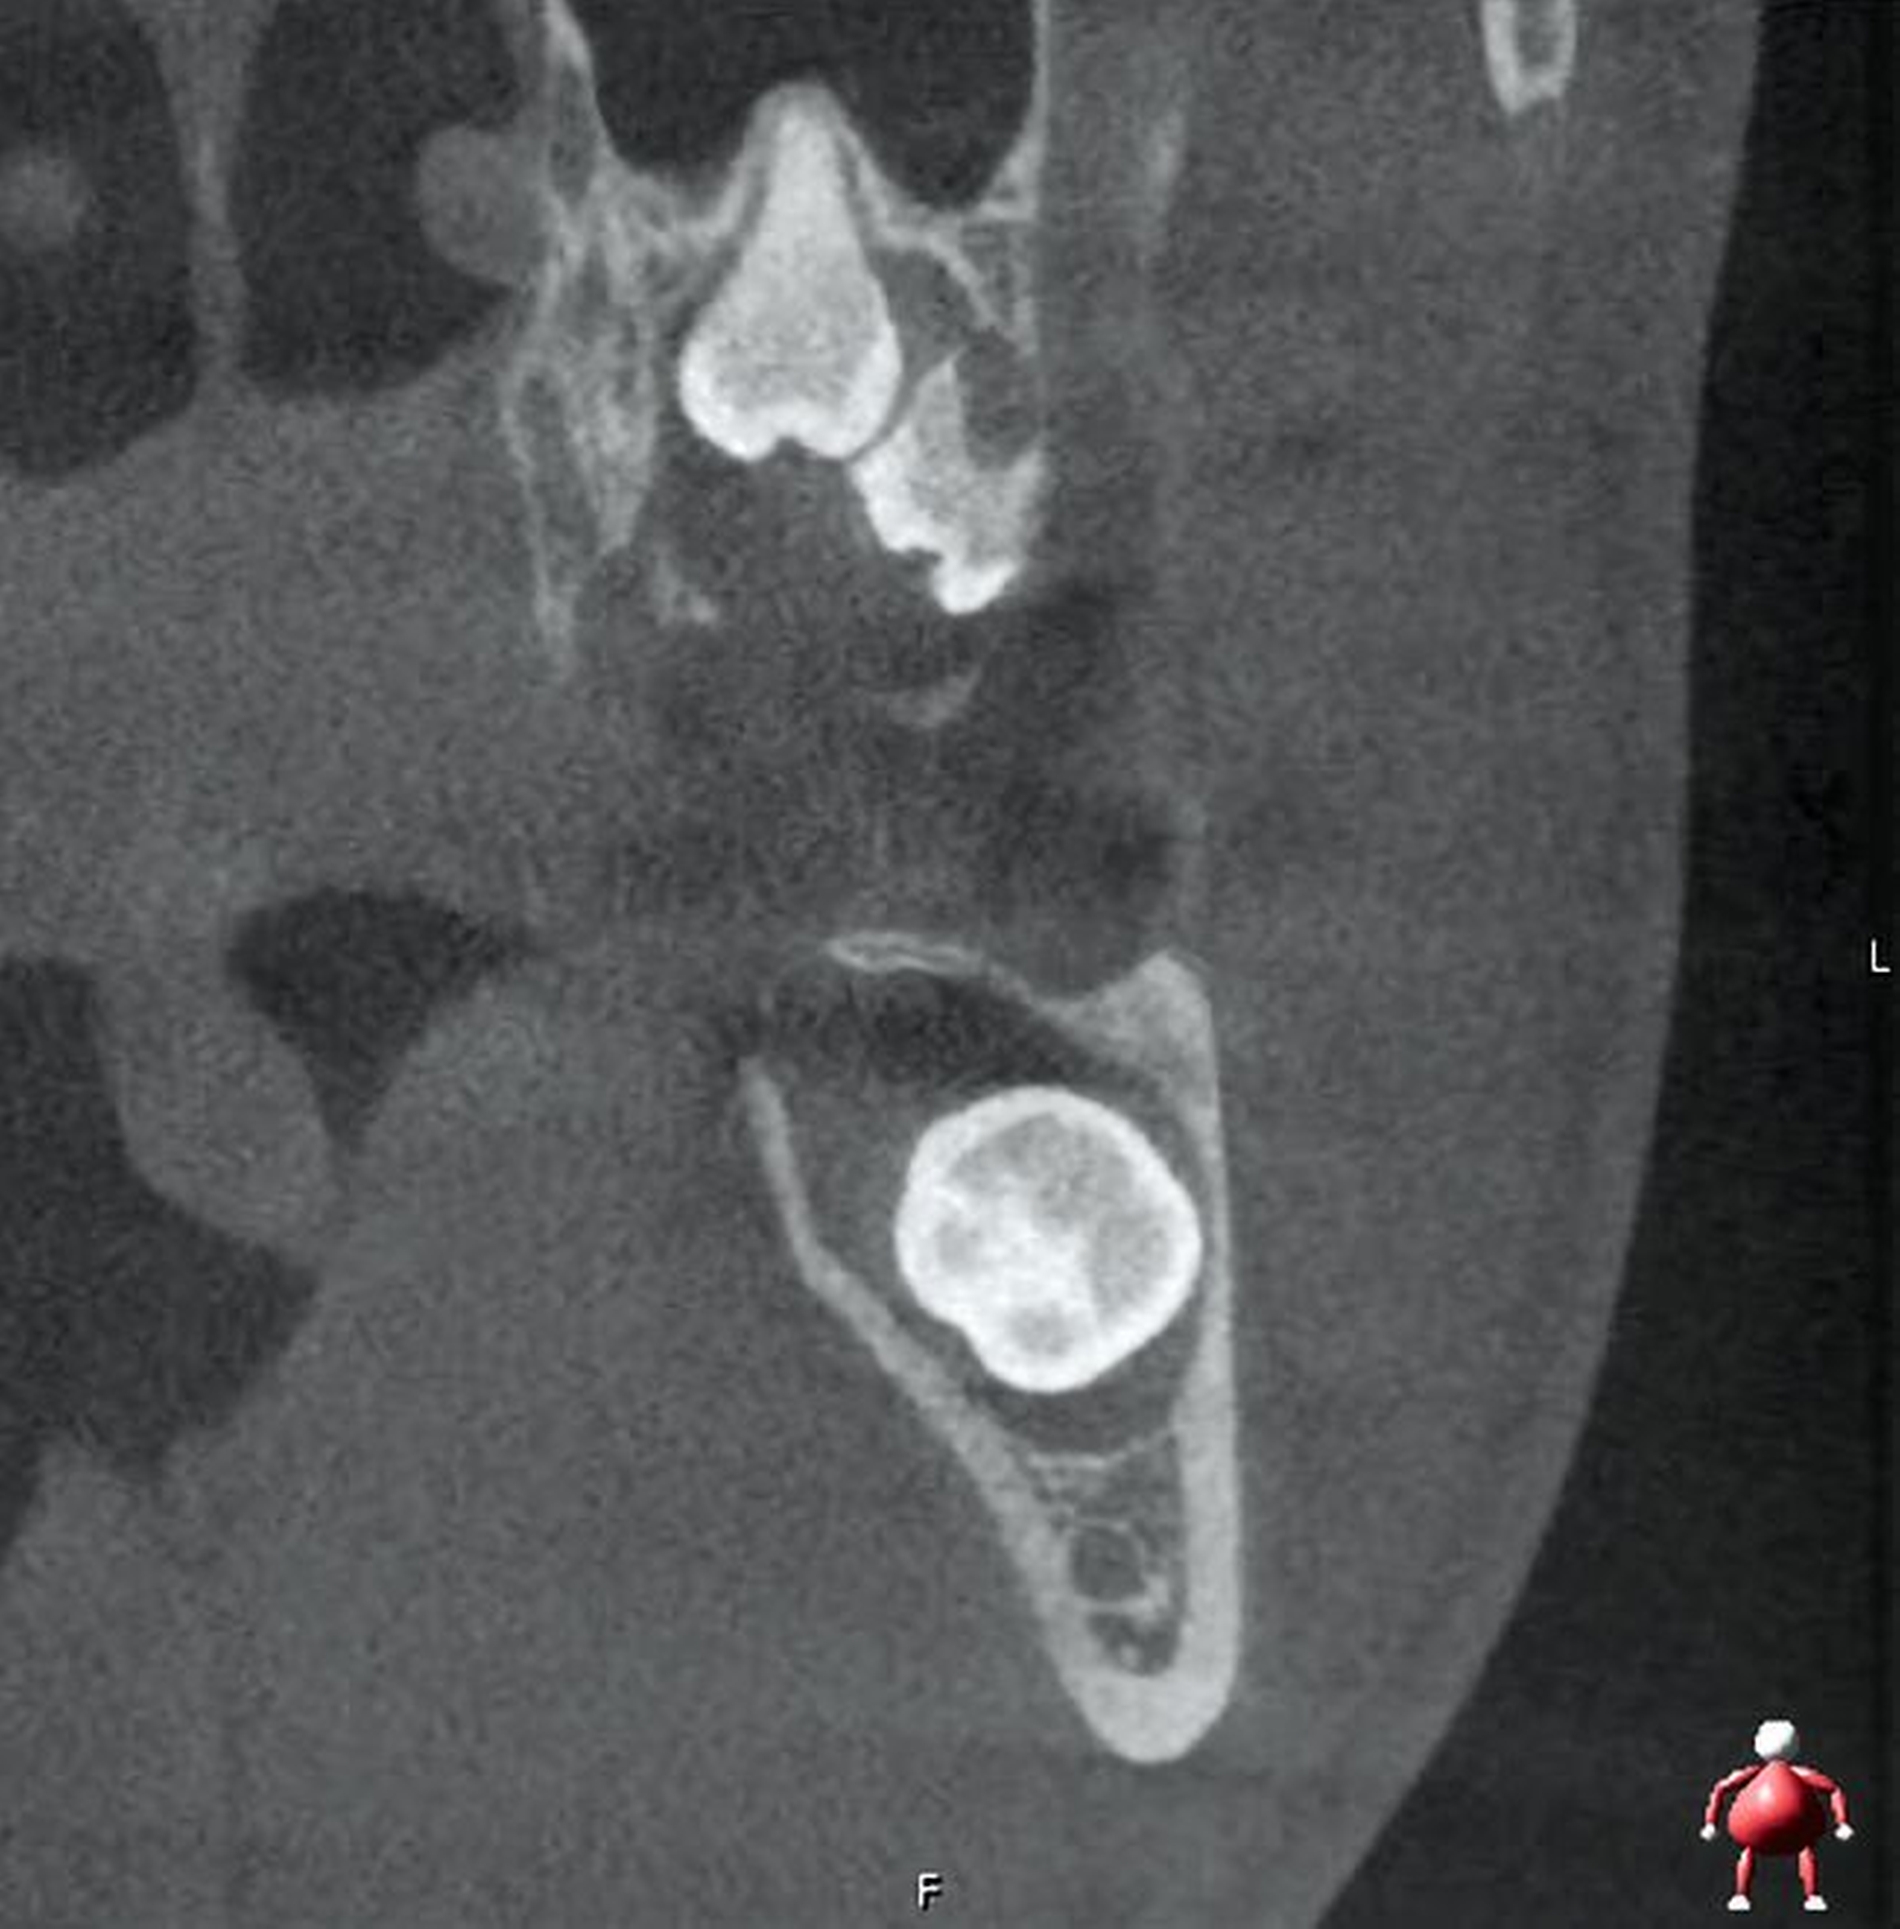

Im Unterkiefer linksseitig zeigt sich der Canalis mandibularis lingual verlaufend, in enger Lagebeziehung zur Wurzel des retinierten und ebenfalls nach mesial gekippten Zahnes 38 (Abbildung 3).